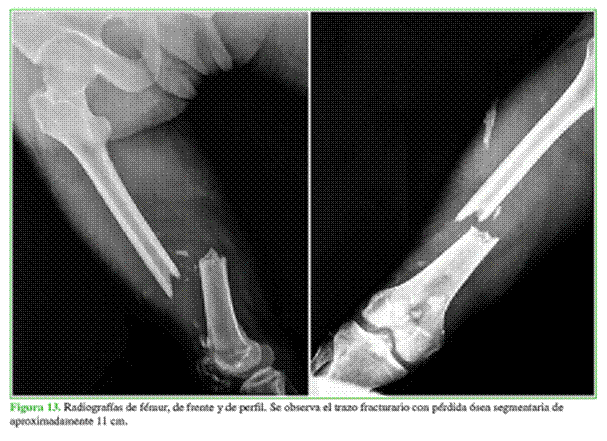

Hombre de 22 años, derivado al hospital con valva de yeso a las cinco semanas de haber sufrido un accidente automovilístico. Tenía una fractura diafisaria de fémur expuesta por la cara anterior con defecto segmentario de aproximadamente 10 cm, fractura conminuta de rótula homolateral (Figura 13) y lesión en el plexo braquial.